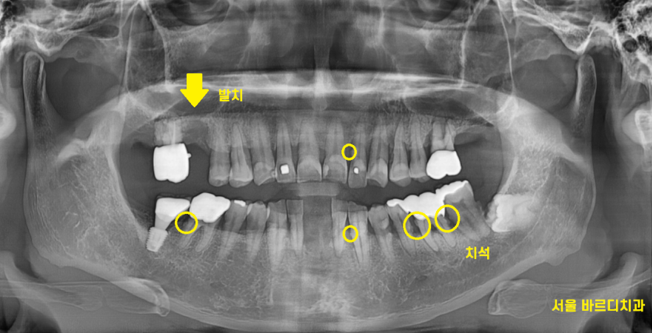

230511

x-ray상에서 치석이 관찰될정도면

왕 치석이라는 얘기입니다.

잇몸 관리 한지 오래 되셨다는 말이죠.

처음에는 조그맣게 뭉쳐있던 치석이

점점 몸 크기를 키워 x ray에 보일정도로...

오른쪽 어금니 시림으로 내원하셨지만

다른 치아들도 무너지기 일부 직전의 상황

잇몸이 한번 말썽을 부리면 1개의 치아에서 안끝납니다.